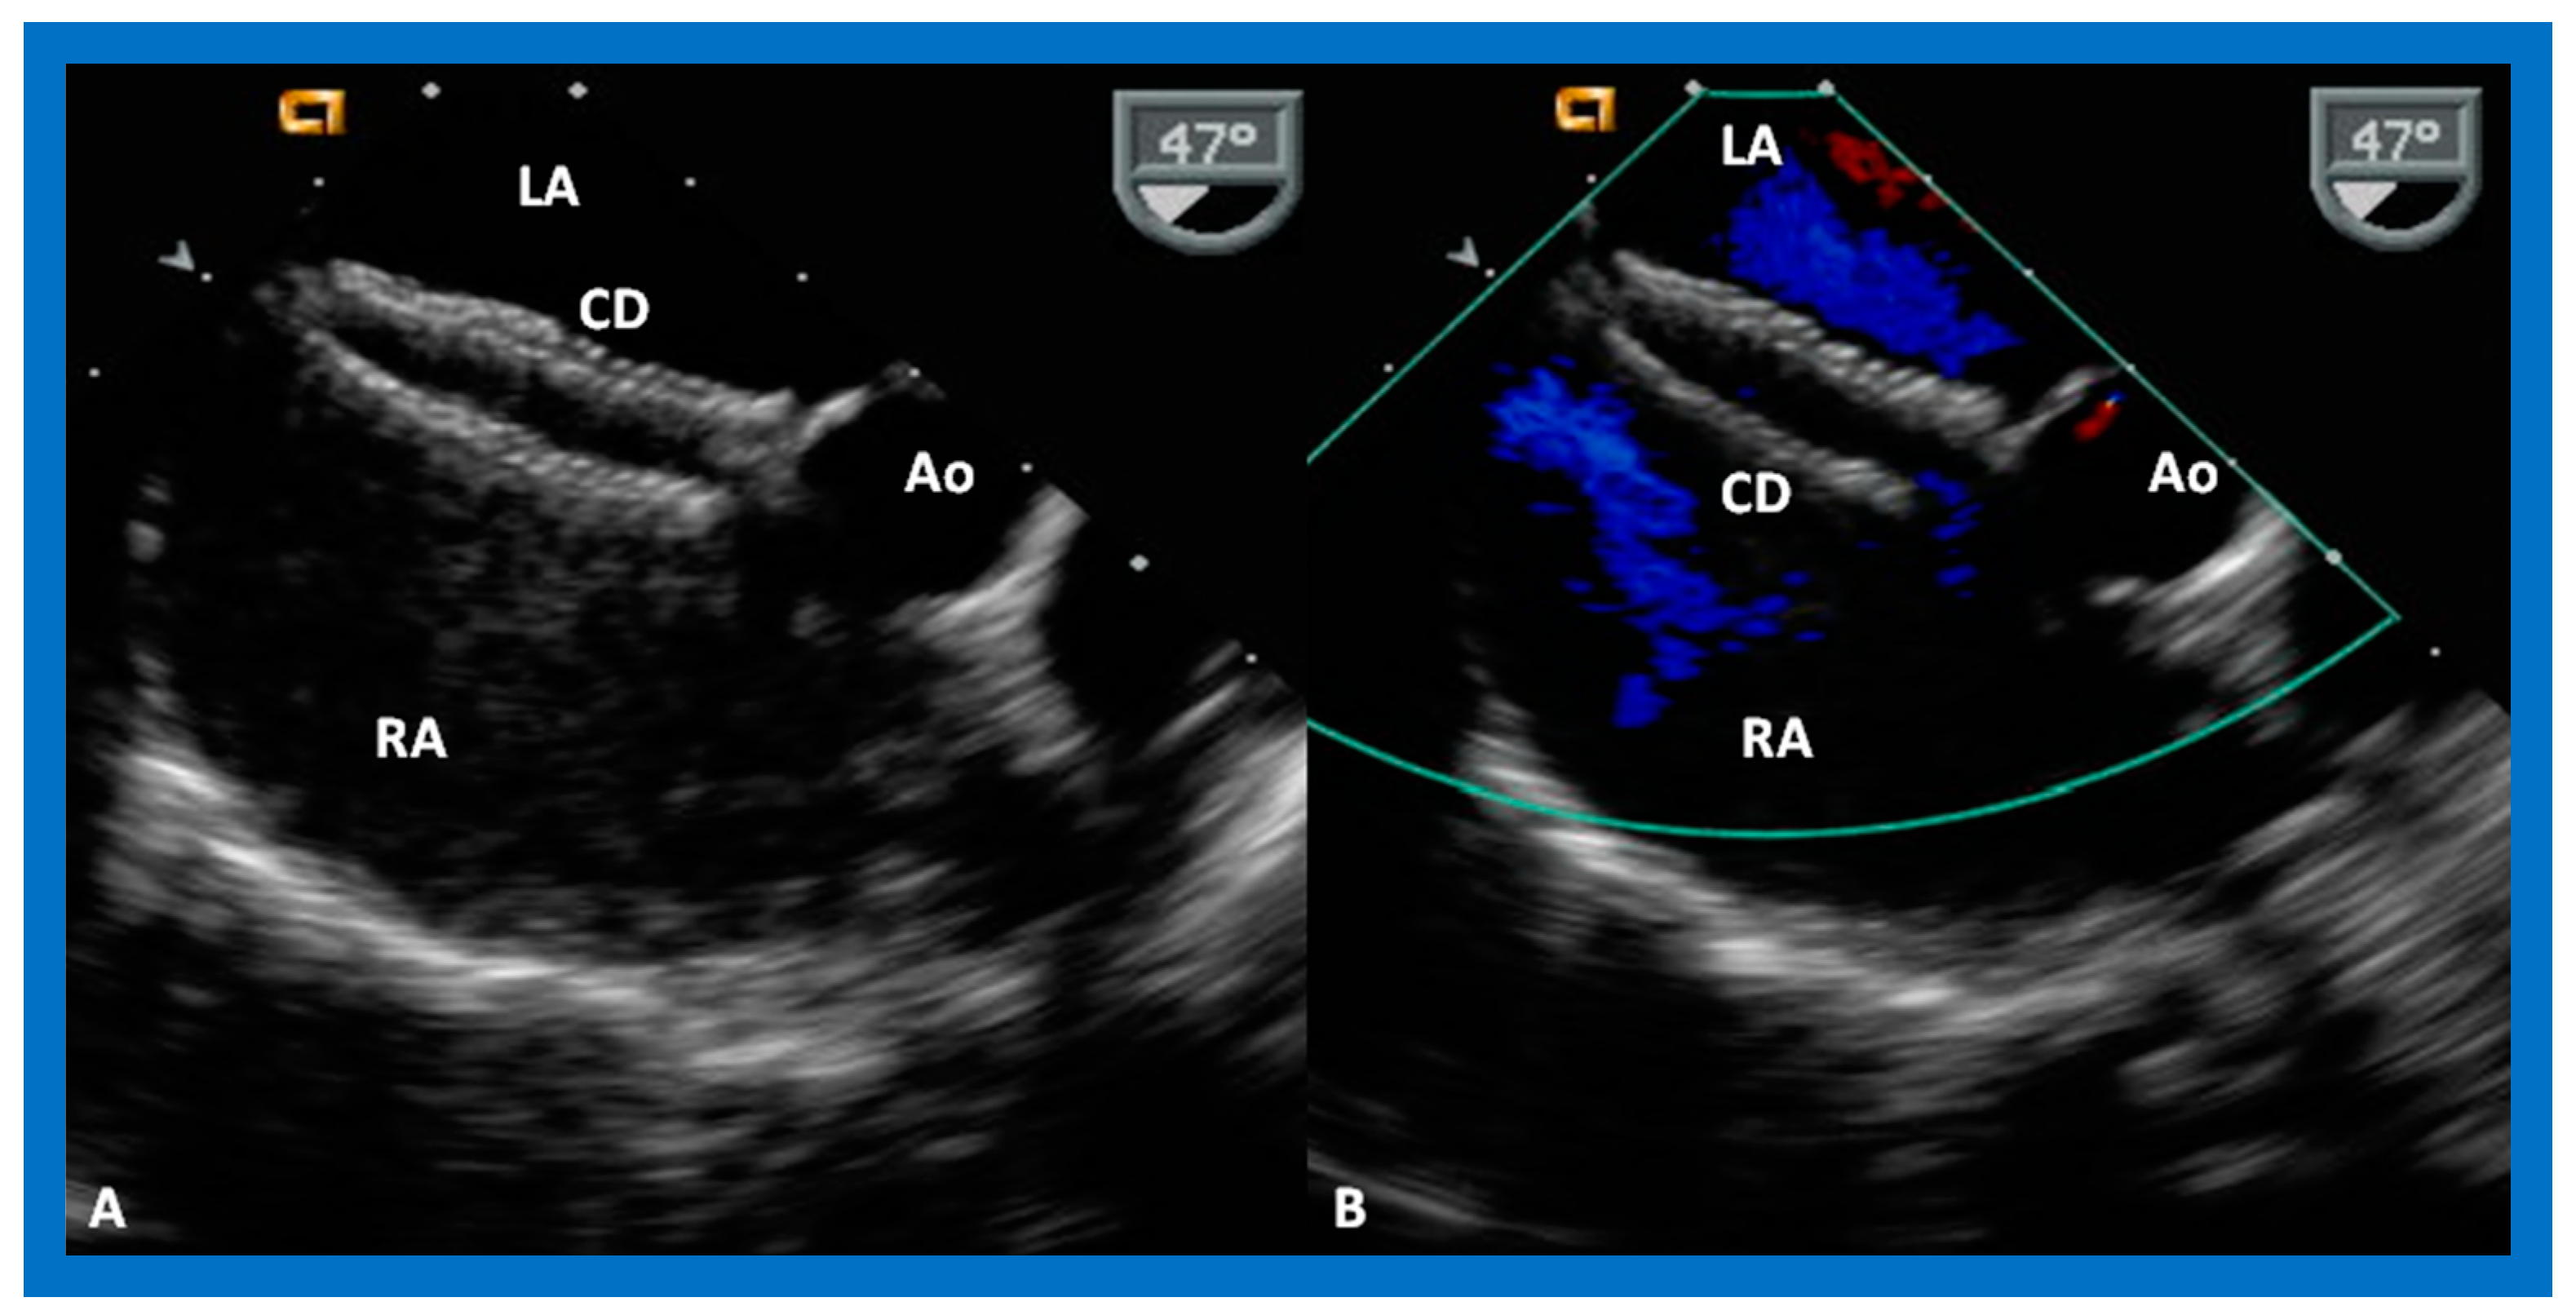

9.4. Residual Shunts

9.6. Obstruction of Systemic and Pulmonary Venous Drainage

8. Device Occlusion